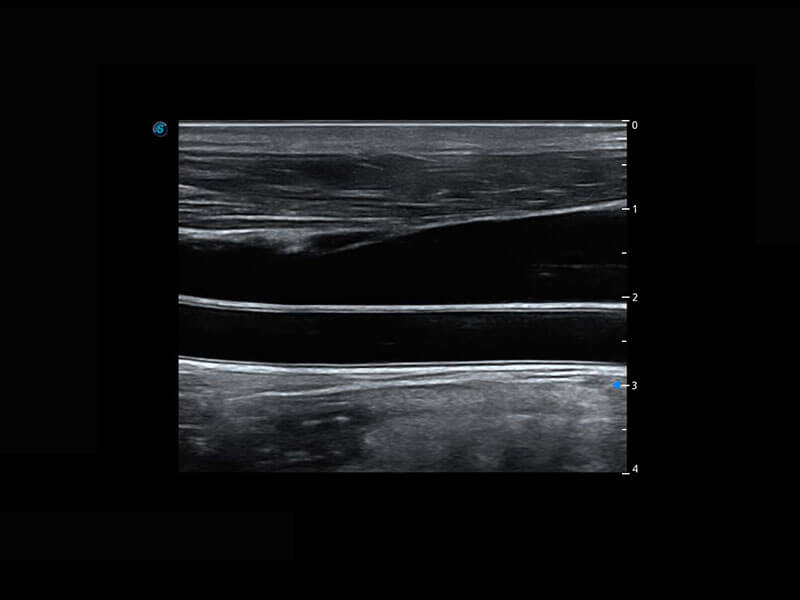

P60搭载宽频带线阵探头、宽景成像、弹性成像技术,为您提供乳腺应用方案。P60支持高频相控阵探头、线阵探头、腹部高频探头、腹部微凸探头等,丰富的探头群搭载敏感的彩色血流成像,适用于新生儿多种脏器检测要求,满足新生儿筛查需求。

乳腺导管癌

乳腺癌显微血流